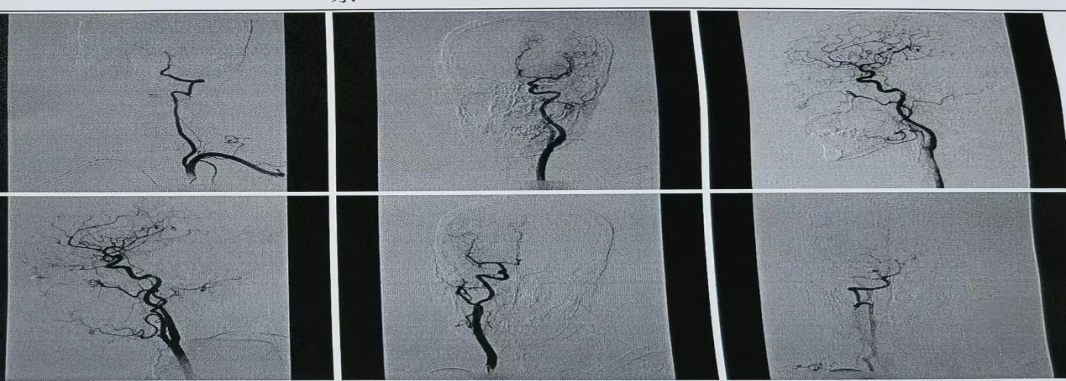

首例经桡动脉全脑血管造影术,实现富平县乃至渭南市此领域诊疗技术的新突破。

患者以肢体无力就诊,颅脑核磁提示颅内动脉多发节段性狭窄,明确诊断为多发脑梗死。王乐医师指导受援科室介入团队采取经“桡动脉全脑血管造影术”,明确患者脑血管狭窄情况。取得患者及家属充分知情同意后,手术用时不到1小时,过程顺利,患者生命体征平稳,术后即刻下床,活动自如。术后6小时拆除桡动脉压迫器,穿刺处无渗血渗液及硬结,搏动正常,患者无任何不适。

全脑血管造影术是评估脑血管的“金标准”。经桡动脉全脑血管造影术是近年来较先进的脑血管检查技术,为脑血管疾病的诊断和治疗提供重要依据。经桡动脉穿刺较传统经股动脉穿刺具有以下优势:一、穿刺点损伤小,术中及术后并发症少,术后护理方便安全;二、术后患者即刻下床活动,舒适度好,易于接受,尤其对于肢体瘫痪或高龄的老年人;三、术后下肢不需长时间制动,避了下肢深静脉血栓的形成,不影响患者康复锻炼及其他治疗。